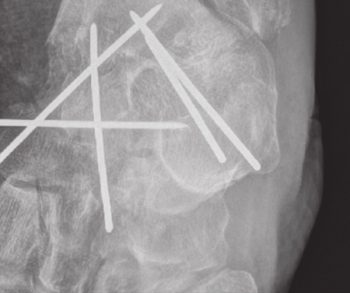

Patient presents with hip pain. Can you make the diagnosis?